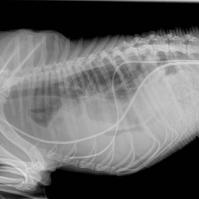

Thoracotomie

Exploration thoracique

Drains thoraciques